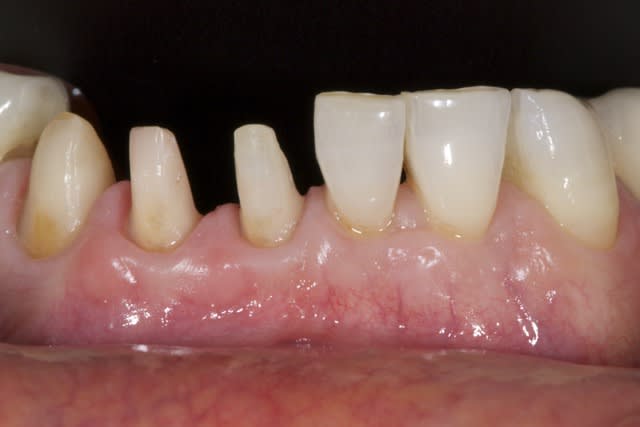

tient un boulot ou il y a un peu de tout.

bridge antérieur , car la pose d'implants nécessitait de la reconstruction trop importante, endo couronne sur les molaires mandibulaires par manque de hauteur, onlay. implants à la mandibule.

A noter les 2 PM maxillaires qui comportaient

chacune 3 canaux.